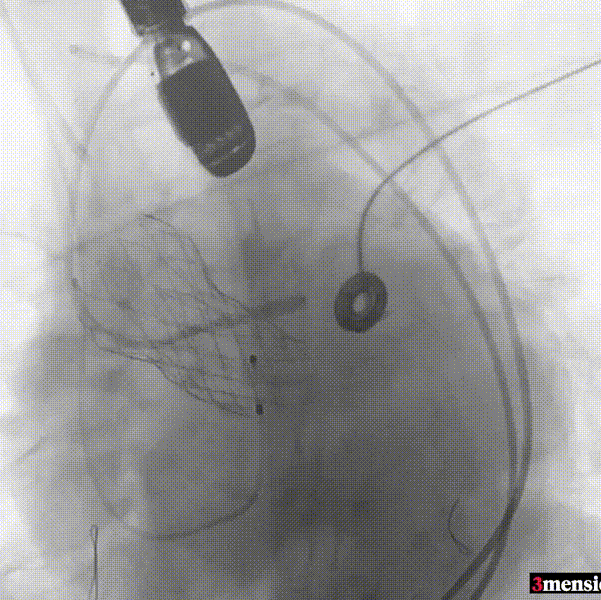

手术过程回顾:

患者全麻后,右侧股动脉建立主入路,主动脉根部造影显示主动脉瓣明显钙化。心室内轻微反流,主动脉及心脏情况整体较为稳定。直头导丝跨瓣后,在超硬导丝支撑下,瓣膜输送系统顺利跨瓣。在180次/分快速心室起搏下,确定降压至50mmHg后选择18mm球囊进行预扩张。在球囊扩张后,该患者血压未见升高,随即进行胸外按压,同时根据术前评估及球囊预扩情况,选取直径23mm瓣膜果断快速进行瓣膜定位并释放。瓣膜释放后患者心律和血压趋于平稳。

主动脉根部造影

直头导丝跨瓣

球囊预扩

瓣膜定位并行胸外按压

瓣膜释放至工作位

瓣膜脱钩

造影查看瓣膜形态

球囊后扩

最终造影

瓣膜释放后,超声提示患者存在一定的跨瓣压差和反流,通过球囊后扩,患者跨瓣压差即刻显著下降,反流量轻微。术后患者心功能持续得到改善,效果良好,此次手术取得圆满成功。